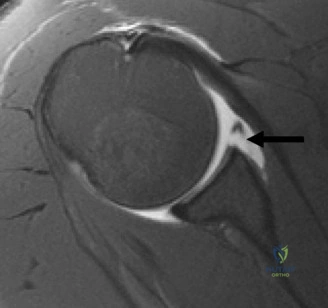

Anterior shoulder instability represents the most common major joint dislocation encountered in orthopedic practice, disproportionately affecting young, active, and athletic populations. While the classic Bankart lesion—an avulsion of the anteroinferior capsulolabral complex—was historically considered the essential lesion of anterior instability, contemporary orthopedic understanding has shifted dramatically toward the recognition of osseous defects. Glenoid bone loss, often occurring in tandem with humeral head defects (Hill-Sachs lesions) to create bipolar bone loss, fundamentally alters the biomechanical stability of the glenohumeral joint and dictates surgical decision making.

The epidemiology of anterior instability highlights a high recurrence rate, particularly in patients under the age of 20 engaged in contact sports. Recurrence rates following non operative management in this demographic can exceed 80 percent. Even following arthroscopic soft tissue stabilization, recurrence rates remain unacceptably high if critical glenoid bone loss is unrecognized or inadequately addressed. The incidence of significant glenoid bone loss in recurrent instability patients is estimated to be between 20 and 40 percent. The morphology of this bone loss typically manifests as attrition or fracture of the anteroinferior glenoid rim, transforming the normal pear shaped glenoid into an "inverted pear" configuration.

Glenoid bone loss compromises the concavity compression mechanism. The anteroinferior glenoid acts as a critical buttress against anterior translation when the arm is in the vulnerable position of abduction and external rotation. Loss of bone in this region decreases the articular arc length and reduces the force required to translate the humeral head out of the fossa. Biomechanical studies have demonstrated that a defect of 20 percent of the glenoid width reduces the resistance to anterior translation by over 30 percent.

The concept of the "inverted pear" glenoid was popularized by Burkhart and De Beer in 2000. Their seminal paper demonstrated that arthroscopic Bankart repair in patients with significant bone loss (defined as the loss of the inferior glenoid contour) resulted in an unacceptable recurrence rate of 67 percent, compared to 4 percent in patients without significant bone loss. This established the absolute necessity of evaluating bone stock prior to soft tissue stabilization.